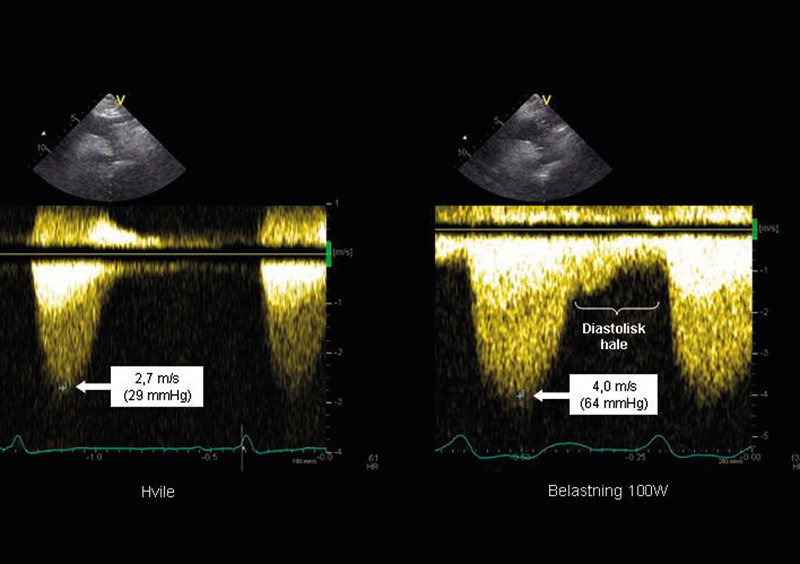

Det er vist at over en tredel av alle pasienter med hypertrofisk kardiomyopati uten utløpsobstruksjon i hvile kan ha signifikant obstruksjon ved belastning (1). Obstruksjonen øker trykkfallet i venstre utløpstractus, og man anser at et maksimalt trykkfall i hvile på > 30 mm Hg og/eller et arbeidsindusert trykkfall på > 50 mm Hg er av klinisk betydning. Disse verdiene blir brukt som grense for behandling med alkoholablasjon eller myektomi (2).

Trykkfallet beregnes fra blodstrømshastigheter registrert med kontinuerlig doppler fra hjertets apeks ved hjelp av den forenklede Bernoulli-likningen ΔP = 4v² (der ΔP er trykkfallet målt i mm Hg og v er maksimal blodstrømshastighet målt i m/s) (3).

Obstruksjonen i utløpstractus kan føre til at fremre mitralseil trekkes fremover i systole og forårsake såkalt SAM-fenomen (systolic anterior movement). Dette kan igjen gjøre det trangere i utløpstractus, med ytterligere økning av trykkfallet, og det kan også oppstå en betydelig mitralinsuffisiens. Blodstrømmen fra denne mitralinsuffisiensen kan være lokalisert nær blodstrømmen i utløpstractus, slik at det kan være vanskelig å skille disse. Ofte får man deler fra begge hastighetssignaler i samme registrering. De kan imidlertid differensieres ved at blodstrømmen i mitralinsuffisiensen begynner tidligere enn blodstrømmen gjennom utløpstractus og ved at obstruksjonen gir en sensystolisk, kraftig akselerasjon av blodstrømshastighetene, med et karakteristisk knivbladformet signal (fig 2).